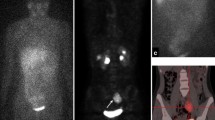

On the other hand, when the ability to detect every single lesion was tested using a lesion-based analysis, PET imaging could disclose significantly more NB lesions than mIBG scintigraphy combined with SPECT or SPECT/CT in seven out of 10 studies (Table 3) [10, 15,16,17,18, 20, 21]. This difference was more evident in those studies that included patients with high-risk disease and with suspected or ascertained relapse. In this setting, when tumour load and dimensions are often not so conspicuous, PET imaging can identify even small lesions often not detected on an mIBG scan [18, 19, 23]. On the other hand, there were no significant differences in the LBA of studies employing [11C]C-HED [15]. Figures 2 and 3 show representative examples of the improved spatial resolution and sensitivity of PET methods over [123I]mIBG scan.

Sixteen-year-old boy affected by NB bone relapse. [123I] mIBG whole-body scan and SPECT/CT (planar and axial images) showed multiple bone localisations (left panels). In the same patients [18F]DOPA, maximum intensity projection (MIP) and axial images showed many small additional lesions (right panels, arrows)